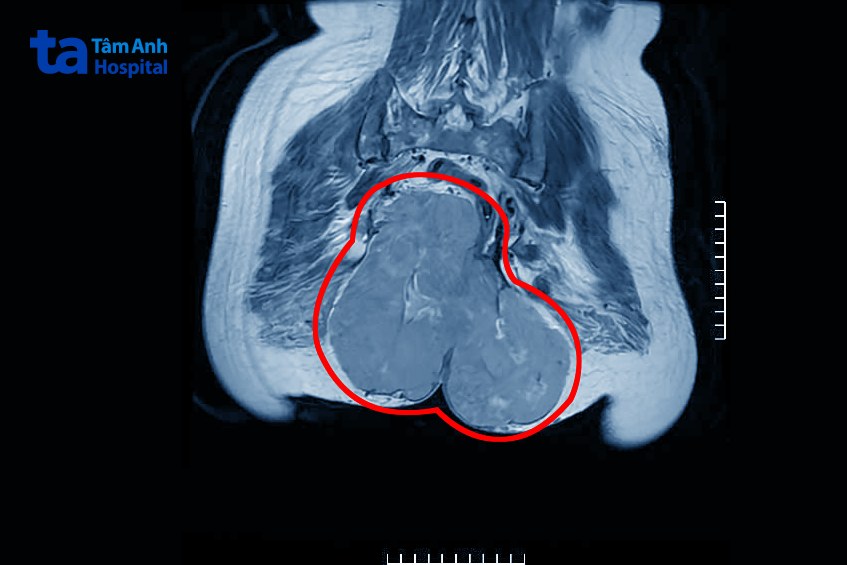

PGS Triệu Triều Dương, Giám đốc chuyên môn Ngoại khoa, Bệnh viện Đa khoa Tâm Anh Hà Nội, cho biết trên chẩn đoán hình ảnh có khối tổn thương kích thước lớn 16,6 x 19,6 cm xuất phát từ tổ chức cơ trơn vùng ranh giới giữa trực tràng và tử cung, phát triển lấp đầy tiểu khung (khu vực dưới rốn) vượt qua tầng sinh môn (khoảng trống giữa hậu môn và âm hộ), xâm lấn cơ nâng hậu môn, cơ mông hai bên, di căn túi cùng tử cung, xâm lấn vào bàng quang, khối u di căn cực trên thận phải kích thước 4,3 x 5,5cm, ngoài ra người bệnh còn có đa nhân xơ tử cung, sỏi túi mật. Xét nghiệm giải phẫu bệnh khối u kết quả dương tính với Sarcoma cơ trơn (Leiomyosarcoma).